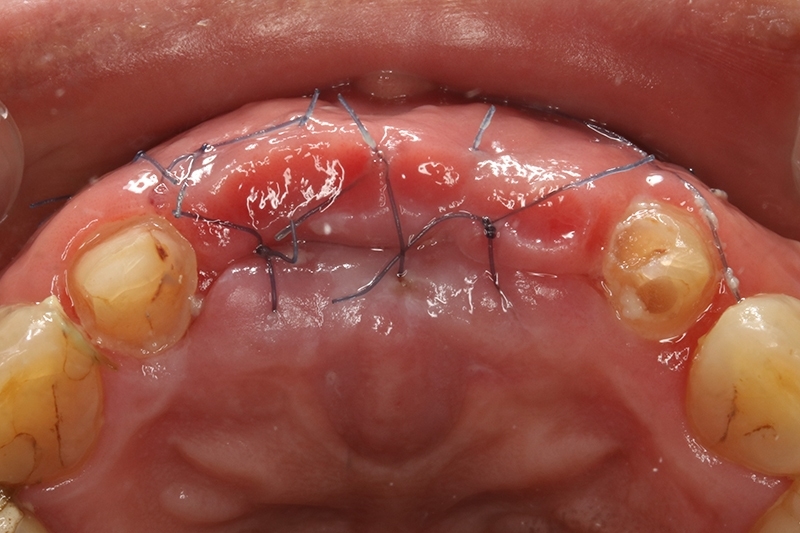

2周後追蹤傷口,癒合良好。

等待6-8個月移除不可吸收再生膜+以數位導板進行植牙手術

移除不可吸收再生膜

可見骨頭生長良好

水平增寬的骨頭,這樣植牙才有理想的三度空間可以置放